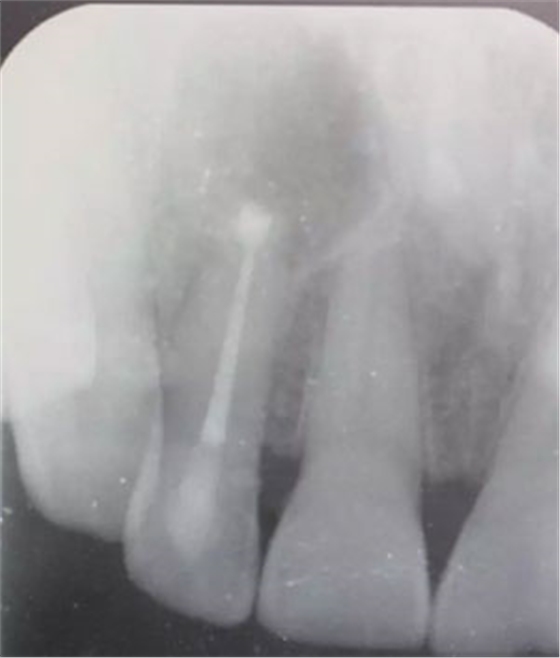

圖1.患者在根管術(shù)前的根尖片影像檢查:12有開髓孔,根尖有橢圓形陰影。

圖21.術(shù)后的x根尖片影像情況。12根尖區(qū)MTA充填完好。